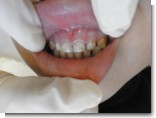

この間抜歯した上の親知らずです。

最近、親知らず関係の患者さんがたくさんお見えになります。

写真ではわかりにくいのですが、普通の歯の1,5~2倍の大きさで

患者さんよりも僕がビックリしました^^。

しかも完全に歯ぐきの中に埋まっていたのでかなり苦労しました。

(しかも根がすごく曲がっている・・) .jpg)

抜歯後はほとんど痛みもなくて経過良好です。